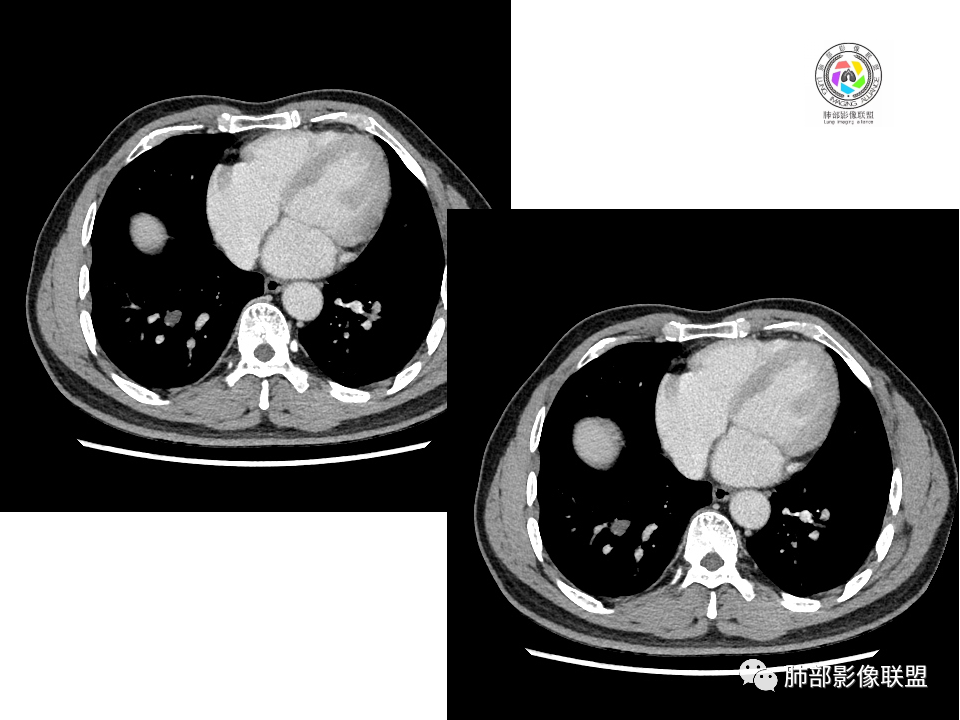

病理结果

病例小结

一.影像与临床:

1.男性,49岁,体检发现。

2.右肺下叶背段胸膜下块影,边界清楚光整,上下极见磨玻璃晕,未见明显分叶毛刺和棘状突起,未见胸膜凹陷或胸壁侵入。密度均匀,轻度不均匀强化。未见支气管进入。

3.右肺中叶外侧段胸膜下散在小片影,磨玻璃密度为主,边界不清,支气管相关。符合炎性特征!

4.右肺下叶基底段支气管血管束旁小结节影,边界清楚,强化不明显。注意,这结节在“遥远的”基底段。

二、综合分析:

显然本例焦点在于背段那个边缘光整的块影!

关于结节型隐球菌

1、普通人隐球菌感染的时相:初期的隐球菌感染周围有晕,晕从多变少,或包裹,或吸收,结节实性区可迅速变大。后期(慢性期)的隐球菌周围无明显晕征,边界较清楚。

2、有些模糊晕消失慢的原因:隐球菌对周围肺组织破坏相对不重,周围所供应的营养不多,增殖也不快,呈局部相安无事的状态。隐球菌消灭之后,肺泡间隔的炎症细胞及间质恢复更慢,所以经常能见到隐球菌外面隐约带细丝的模糊影。

3、卫星灶与“蘑菇兄弟”:诊断隐球菌时,建议找卫星灶,卫星灶可以在遥远的地方。可以是遥远地方的微小结节——“小蘑菇兄弟”。有些远处的卫星灶,通常是不规则饱满实性的,晕征不明显。隐球菌的卫星灶非常“隐”,但发现率高达60%多,诊断价值高。

4、卫星灶距离远的原因:隐球菌卫星灶常很远,推测:一次空气来源隐球菌感染进入双肺多处,部分定居繁殖;距离近的隐球菌“蘑菇兄弟”常常是二次感染。

5、周围毛刺纤维、边缘形态等:坏死包裹会使得结节变圆;结节多缺乏明显的分叶征,缺乏局部突出生长能力;如果出现分叶,是由多处肉芽肿中心形成。没有坏死的局限化,结节只是凑合在一起,常呈方形征;毛刺进入晕区(概念源自南边老师),毛刺较短、较软;周围的晕吸收后,会留下不规则边,外面常残留丝状条索;收缩力较弱,临近胸膜对胸膜牵拉不明显。

6、隐球菌的毛刺消失于晕区的解释:隐球菌结节周围有间质淋巴细胞增多,肉芽肿性炎延伸,以及纤维组织增生,形态并不规则,不是因为收缩力。

7、其他:隐球菌实性区相对腺癌更实,一旦实变里面就没空气,胸膜牵拉线(小叶间隔)拉的不太紧。

——摘自王兆宇老师《肺结节CT及病理诊断》高级学习班(肺部影像联盟)